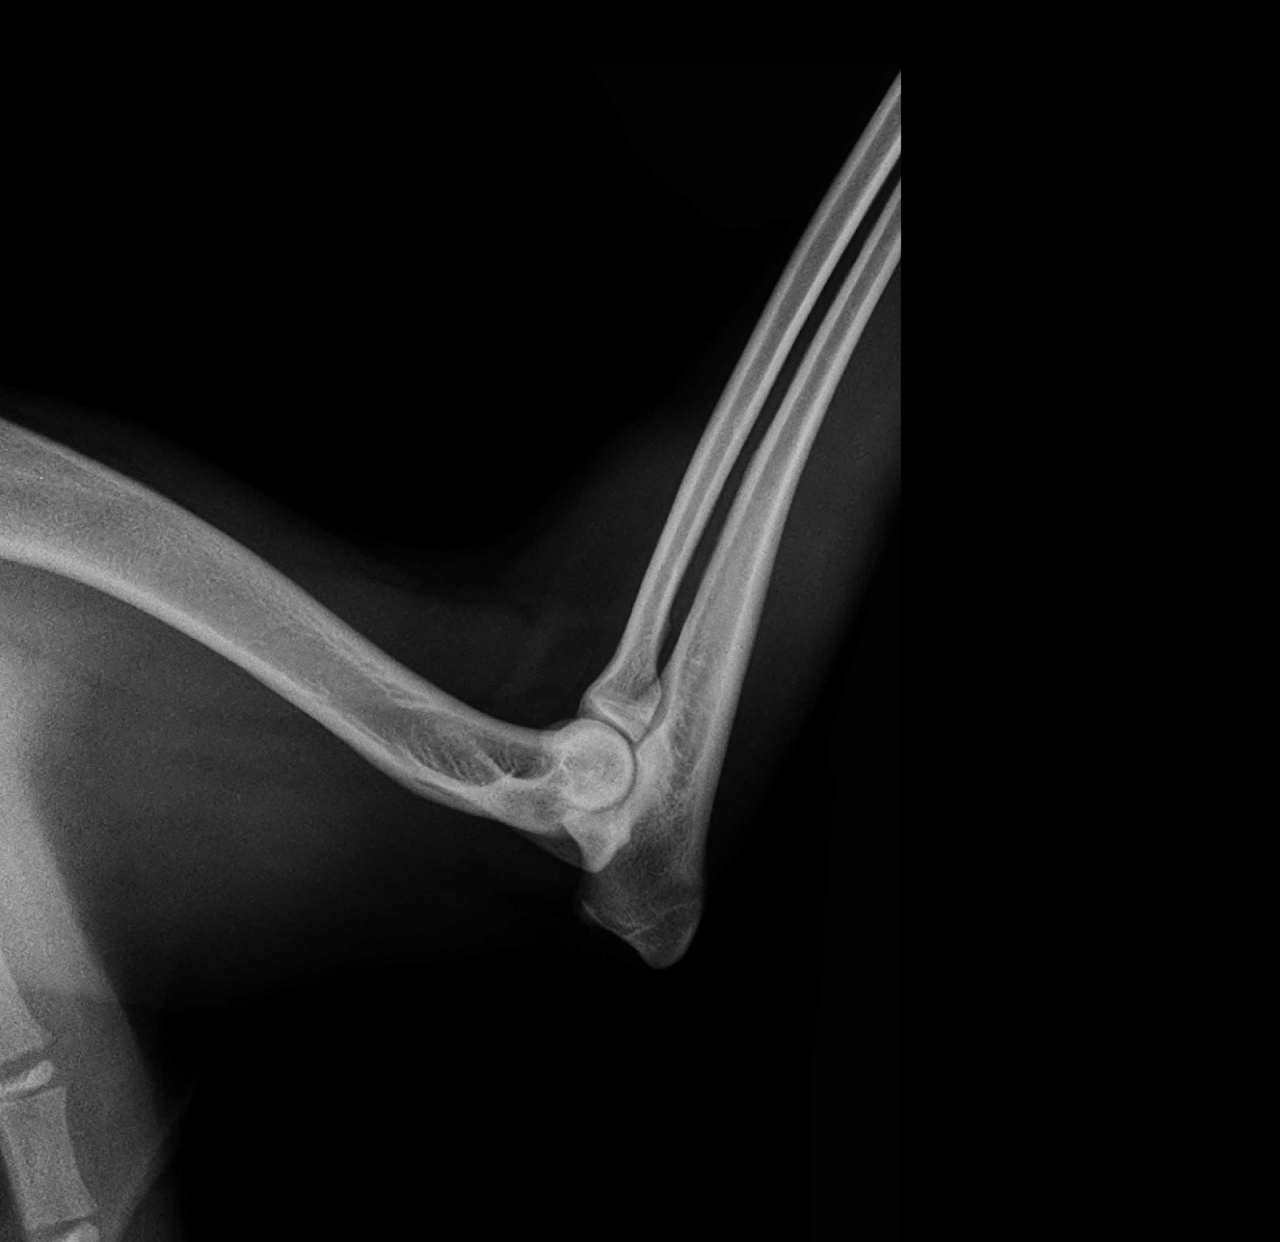

Je stejně jako DKK vývojové onemocnění loketního kloubu. Stejně jako u DKK na rozvoj onemocnění má vliv dědičnost, rychlost růstu, výživa, zátěž. Postižena bývají většinou střední a velká plemena psů. Loketní kloub má složitou strukturu a uspořádání. Dysplazie lokte je souhrný název pro 3 různé patologické stavy. FCP – fragmentovaný procesus coronoieus (oddělení koronoidního výběžku) UAP – volný ankoneální výběžek, OCD – osteochondróza hlavice pažní kosti. Soubor těchto onemocnění se pak projeví kulháním, vybočením končetiny od těla, bolestivostí a odlehčováním končetiny. První příznaky lze pozorovat už v období 4-6 měsíců věku. Pokud se problém diagnostikuje brzy, lze toto onemocnění chirurgicky řešit. Pro potvrzení diagnózy je nutné provést RTG vyšetření.

DLK má rovněž několik stupňů dle závažnosti postižení.

0 – normální loketní kloub bez abnormalit

1 – mírná artróza, formace osteofytů, které nejsou širší než 2 mm

2 – střední artróza, formace osteofytů 2- 5 mm

3 – těžká artróza , osteofyty širší než 5 mm, fragmentace processus coronoideus